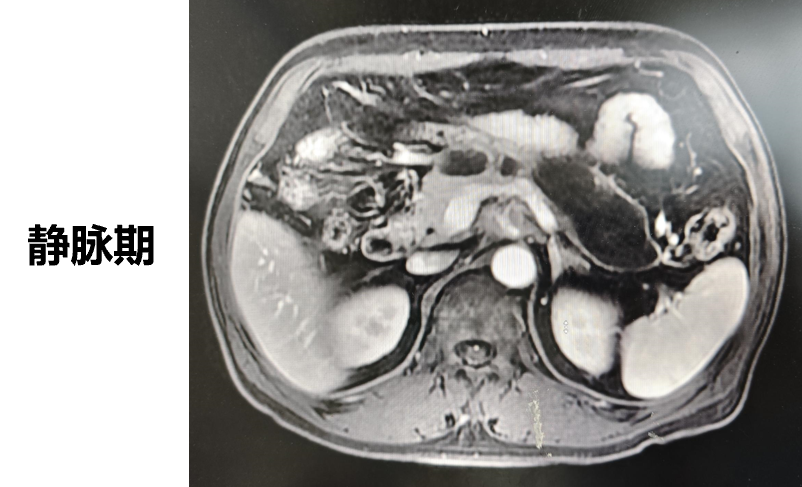

◈ 2023-3-9 上腹部MR增强扫描,对比2023-1-19上腹部MR:胰周多发囊性病变,考虑为术后改变(活检后),假性囊肿形成可能,较前吸收缩小;肠系膜上动脉、腹腔干近段及局部分支周围软组织影,较前缩小,研究者评估整体疗效为部分缓解(PR)。

2023-3-9上腹部MR增强扫描—TTFields联合化疗治疗五月余